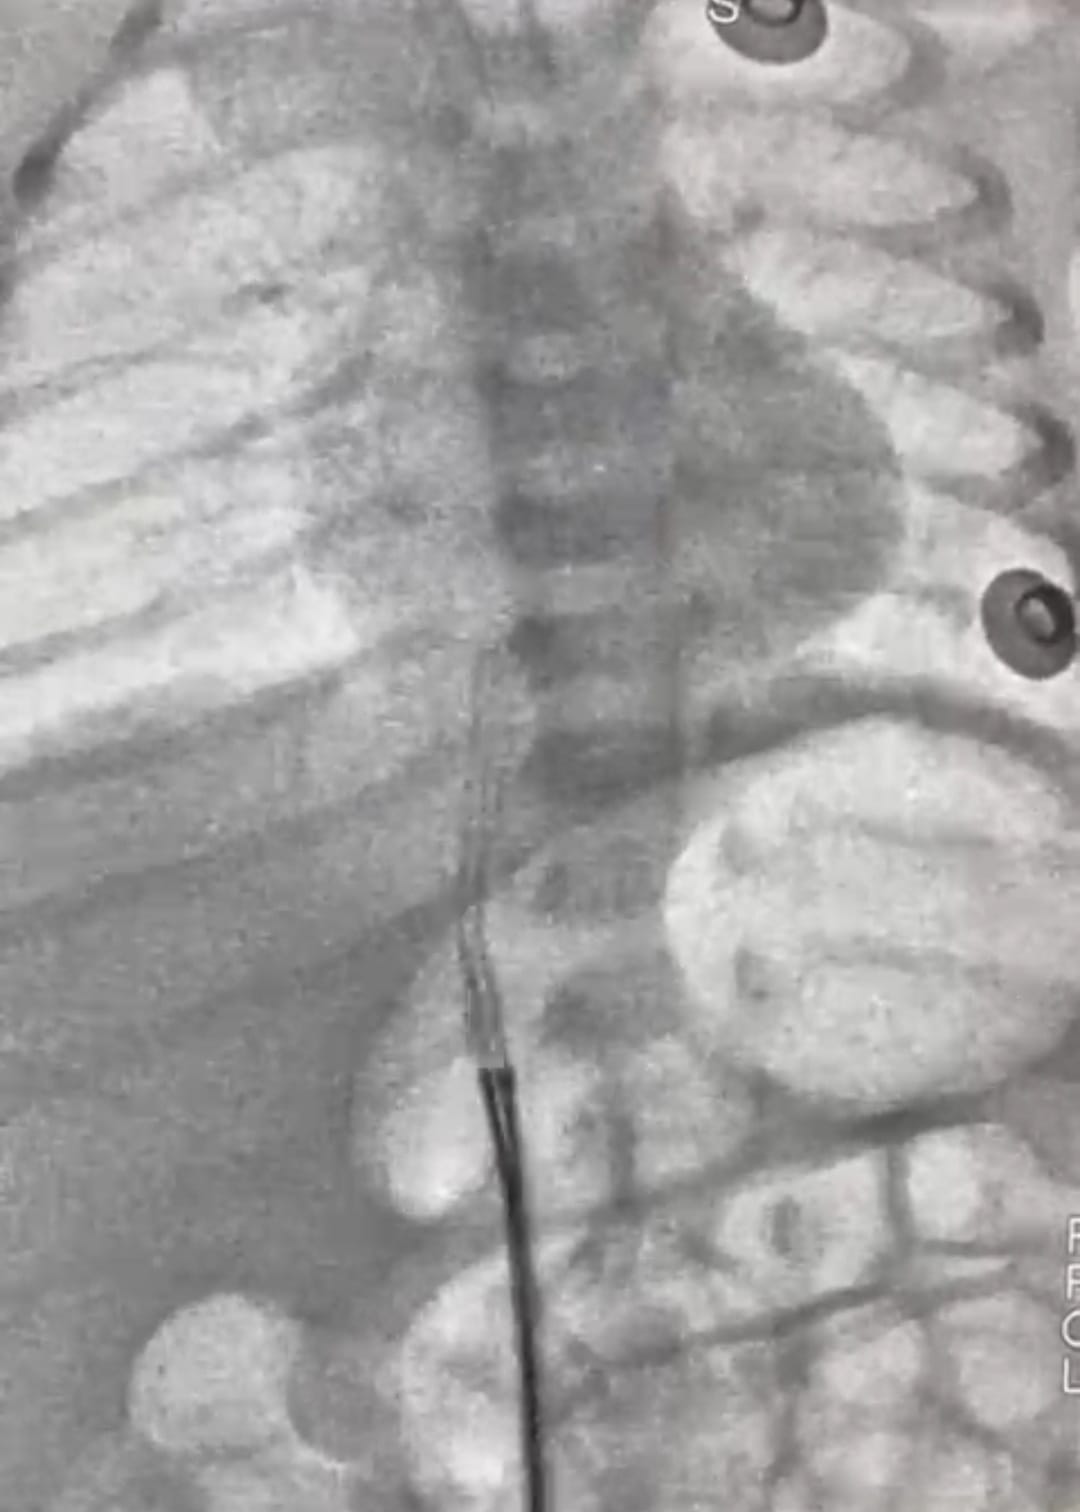

وأفاد الدكتور محمد عبد الهادى عميد معهد القلب القومى بأن طفل حديث الولادة، يبلغ من العمر 5 أيام فقط، قد وصل إلى المعهد في حالة حرجة، بعد أن تحرك جزء من قسطرة السرة من مكانه واستقر في قلب الطفل، وهذه القسطرة تستخدم أحياناً لإدخال السوائل والأدوية، وقد استدعت هذه الحالة تدخلاً سريعًا ودقيقًا، وعلى الفور قام فريق عمل الحضانة،، فى التنسيق لدخول الحالة أول أيام العيد وتجهيزها للتدخل الجراحى، وقام فريق طبي متميز بإجراء القسطرة العاجلة للرضيع. وبفضل الله ومهارة الفريق الطبي، تم استخراج قسطرة السرة بنجاح ودون مضاعفات، والرضيع الآن في حالة مستقرة، وقد غادر الحضانة إلى منزله في حالة جيدة وبدون أي مضاعفات.

وأضاف عميد المعهد أنه ساهم في هذا الإنجاز الطبي فريق متكامل من الأطباء والتمريض والفنيين من أبناء المعهد تحت قيادة أ. د. أحمد معوض الإمام إستشارى القلب وقسطرة العيوب الخلقية بالمعهد، وأ. د. رشا حسني.. رئيس قسم التخدير، وأ. د. أحمد جمال ندا.. زميل التخدير، د. هبة وشاحى .. استشارى الحضانات والرعاية، ود. أحمد أبو هاشم ود. محمود صديق، ود. نعمة إبراهيم، ود. جهاد محمود.